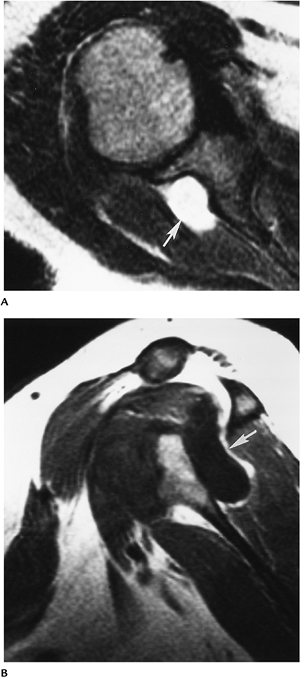

P.501

FIGURE 7-42 Axial T2- (A) and sagittal T1-weighted (B) images demonstrating a ganglion cyst (arrow) compressing the suprascapular nerve.